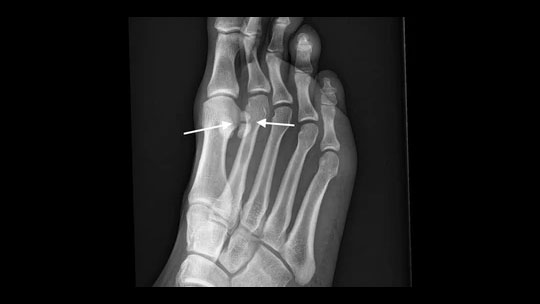

In order to diagnose whether or not you have a Sesamoiditis Fracture your doctor or podiatrist will have to perform a physical exam. He or she may also order X-rays in order to ascertain the amount of damage.